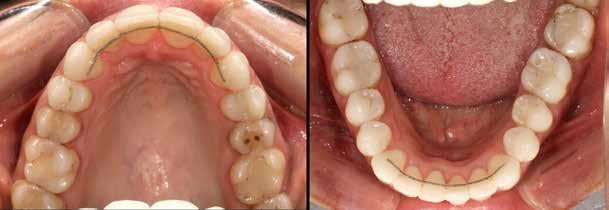

A fogszabályozás aktív fázisa után minden kezelésnél a retenció, a passzív helyben tartó fázis legalább annyira fontos, mint az előtte történtek, továbbá a fogak pozíciójának, de a beállított harapás stabilitásának a segítése is.

Előbbi elérésében az ún. essix retainerek, az egy fogívre kiterjedő mélyhúzott sínek tartják a felső és alsó fogívben a fogakat a beállított pozíciójukban, a felső és alsó frontfogakra orálisan ragasztott fix retainerek mellett (15. kép).

A harapás sagittális rögzítésében elengedhetetlen szerepe van az ún. Pitts Izom Tréning Splintnek, amelyben a páciens összeharap, így az megakadályozza az alsó fogsor visszamozdulását a disztálharapásos helyzetbe (16. kép).